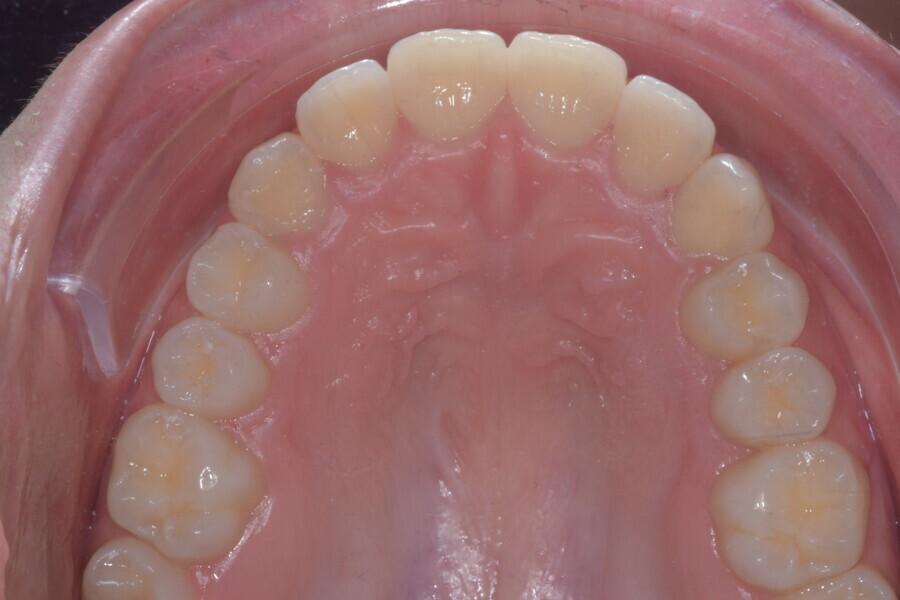

A 14-year-old female patient presented with the chief complaint of midline deviation and dental crowding in both arches. Facial analysis showed a hypodivergent growth pattern, a normal nasolabial angle, a harmonious profile and proper chin projection. Clinical examination revealed a Class III skeletal relationship (ANB = 0°) and Class I molar relationship. The maxillary right canine was absent, and this had led to space loss and mesial drift of posterior teeth on the right side, resulting in a slight Class II molar relationship. The maxillary left canine had erupted in a high position. The mandibular arch displayed crowding despite the agenesis of the right second premolar and the persistence of the primary molar (Figs. 3–11). The radiograph showed the probably premature loss of the maxillary right primary canine and consequently impacted maxillary right permanent canine, and the agenesis of the mandibular right second premolar and the mandibular right third molar (Fig. 12).

Fig. 3